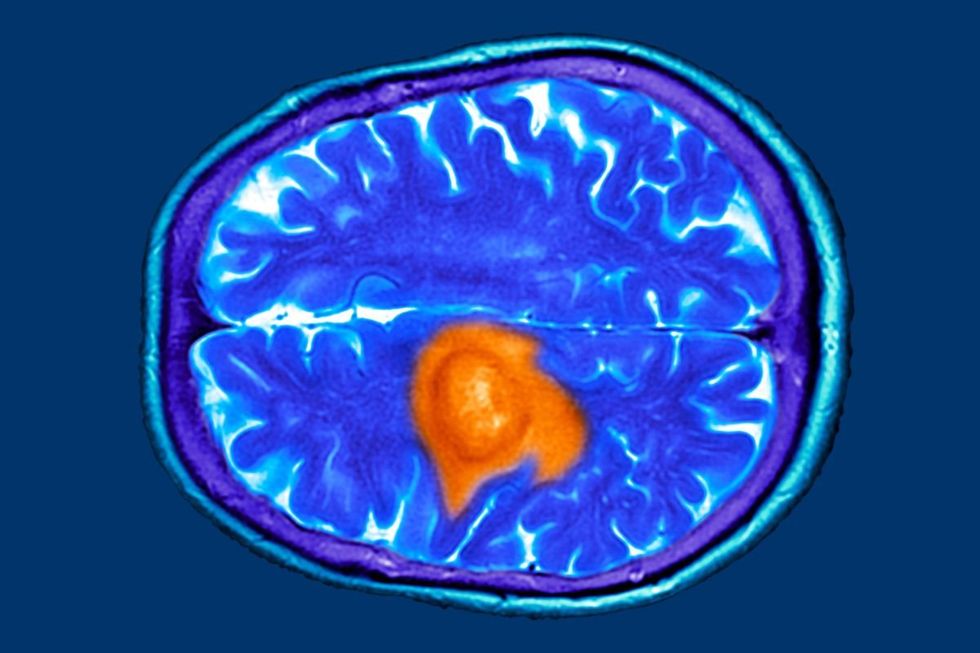

Tau protein deposits in the brain are closely associated with dementia, making these findings particularly noteworthy for those concerned about cognitive decline in later life.

Tau protein deposits in the brain are closely associated with dementia

|GETTY